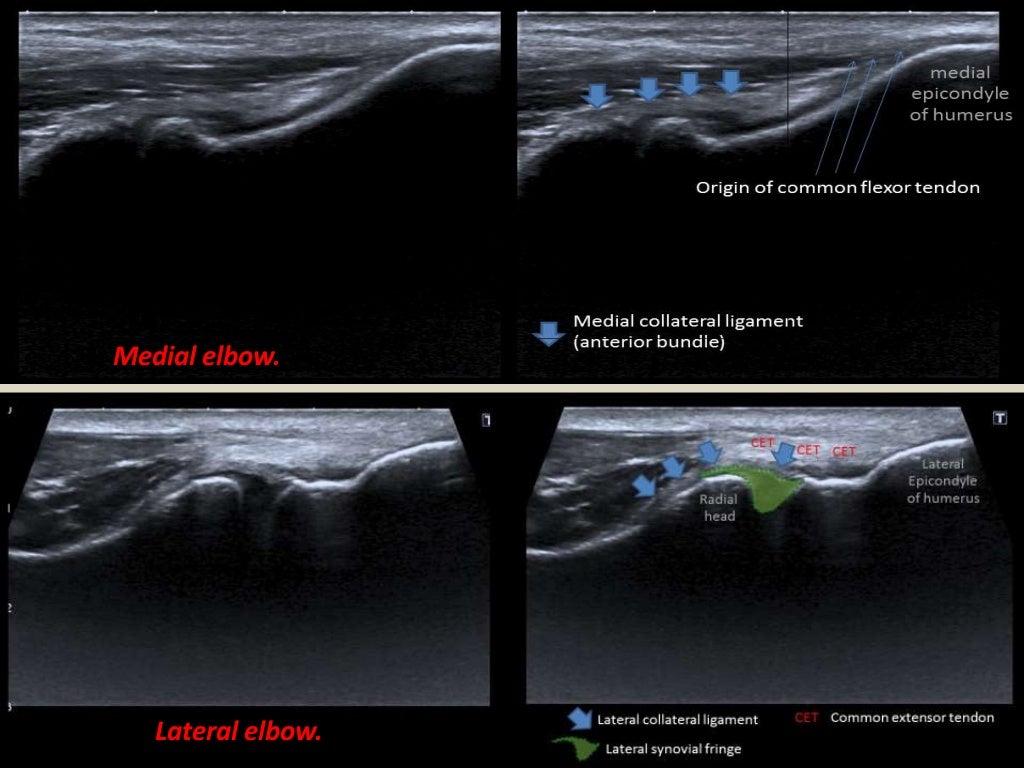

Medial Elbow Ultrasound Elbow Joint Ultrasound Full elbow extension can be obtained by placing a pillow under the joint. The linear high frequency transducers allow for great image resolution. Transverse plane at the level of the humerus. The white arrows indicate the radial and coronoid fossae. This powerful imaging tool has the advantages of. Ultrasonography (us) has become an important imaging modality for evaluating pathologic conditions. Elbow Joint Ultrasound.